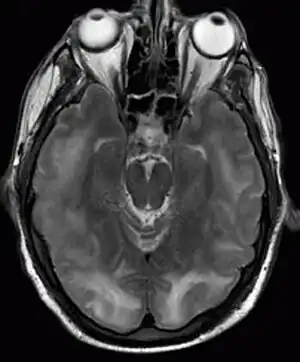

| Posterior reversible encephalopathy syndrome visible on magnetic resonance imaging as multiple cortico-subcortical areas of T2-weighted hyperintense (white) signal involving the occipital and parietal lobes bilaterally and pons. | |

The diagnosis is typically made with magnetic resonance imaging of the brain. The findings most characteristic for PRES are symmetrical hyperintensities on T2-weighed imaging in the parietal and occipital lobes; this pattern is present in more than half of all cases.[1][3] FLAIR sequences can be better at showing these abnormalities.[4] Some specific other rare patterns have been described: the superior frontal sulcus (SFS) watershed pattern, a watershed pattern involving the entire hemisphere (holohemispheric), and a central pattern with vasogenic oedema in the deep white matter, basal ganglia, thalami, brainstem and pons.[1][3] These distinct patterns do not generally correlate with the nature of the symptoms or their severity, although severe edema may suggest a poorer prognosis.[1] If the appearances are not typical, other causes for the symptoms and the imaging abnormalities need to considered before PRES can be diagnosed conclusively.[4] In many cases there is evidence of constriction of the blood vessels (if angiography is performed), suggesting a possible overlap with reversible cerebral vasoconstriction syndrome (RCVS). Diffusion MRI may be used to identify areas of cytotoxic edema caused by poor blood flow (ischemia) but it is not clear if this prognostically relevant.[1][4] Abnormal apparent diffusion coefficient is seen in about 20% of cases.[4]